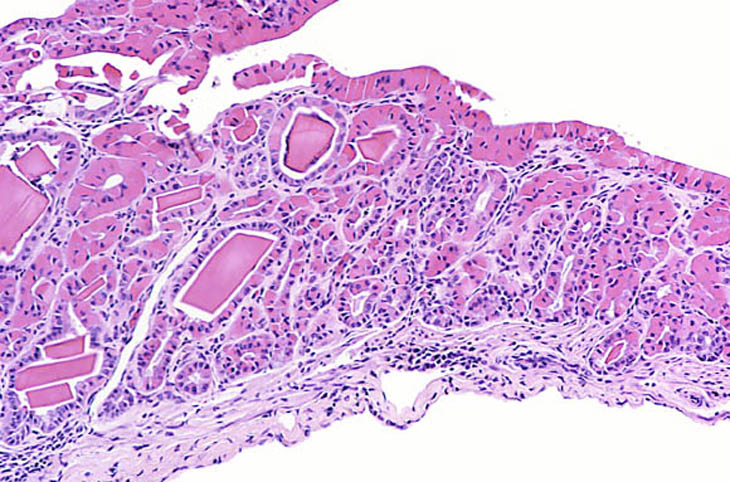

Eosinophilic crystalline inclusions and hyalin degeneration of epithelial cytoplasm in an adenomatous hyperplasia of the gallbladder. High magnification shows the brightly eosinophilic hyalinized cytoplasm of the epithelial cells.